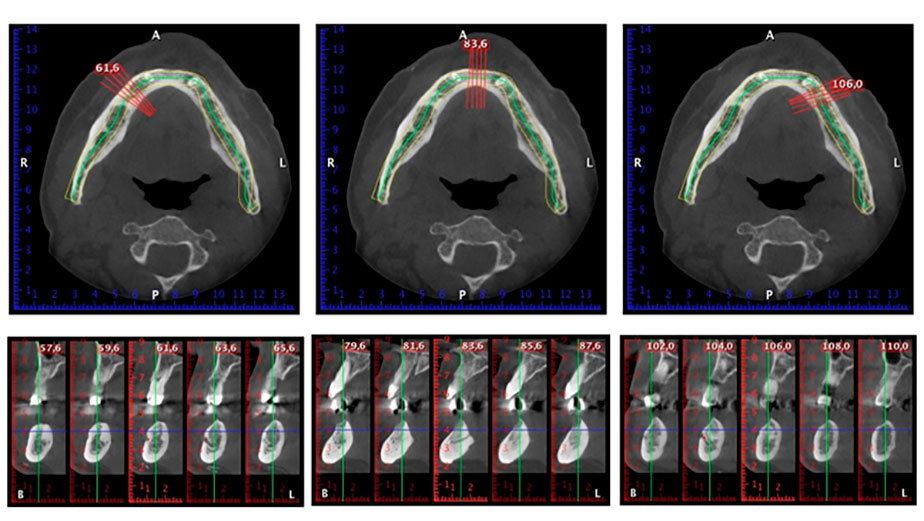

Zur Planung und Risikominimierung wurde eine dreidimensionale Volumentomografie (DVT, Planmeca) erstellt. Dieses zeigte, dass die Qualität und Quantität des Knochens für eine Operation und Sofortversorgung nach der Fast & Fixed-Methode ausreichend war. Nach Protokoll dieses Konzeptes wird in Regio 35, 32, 42 und 45 implantiert. Durch die bis zu 45-Grad-Schiefstellung der distalen Implantate wird das Durchtrittsprofil nach posterior verlegt und ein größeres Stützpolygon erreicht (Abb. 3).